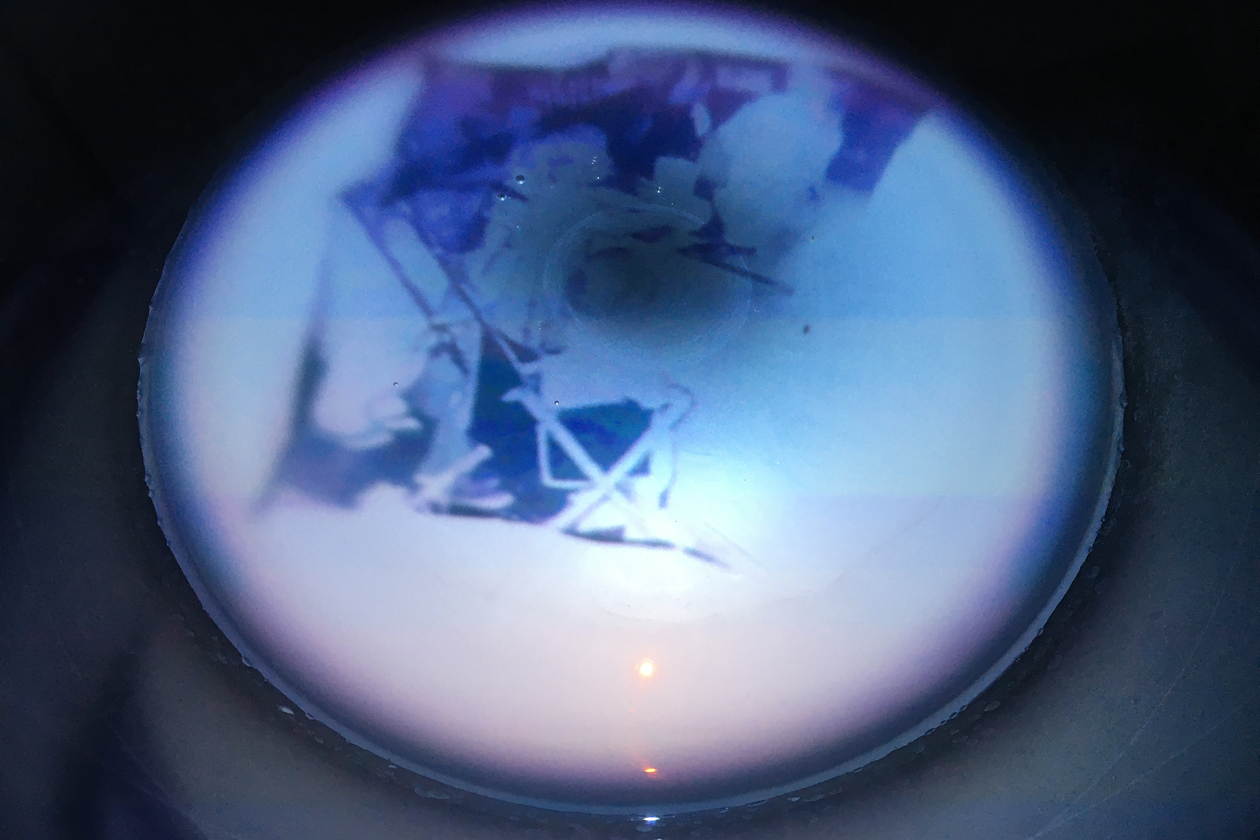

The central premise of this doctoral project is that the progressive cognitive ambiguity that is dementia can be creatively apprehended by way of lostness. As defined by Rebecca Solnit, ‘lost’ holds “...two disparate meanings. Losing things is about the familiar falling away, getting lost is about the unfamiliar appearing.” The initial hypothesis of this research was that in certain neurodegenerative conditions the familiar and unfamiliar can confoundingly combine, and that it’s through the lens of this particular combination that some comprehension of dementia as lived experience may be approached. The disorienting misperceptions most commonly encountered in cognitive decline are visual in nature. Given, then, that dementia reveals the importance of vision to perception, how may the photographic, with lostness as optic, be used to illuminate cognitive decline? In what ways can creatively visualising aspects of neurodegeneration in dementia inform understandings of its existential ambiguities?